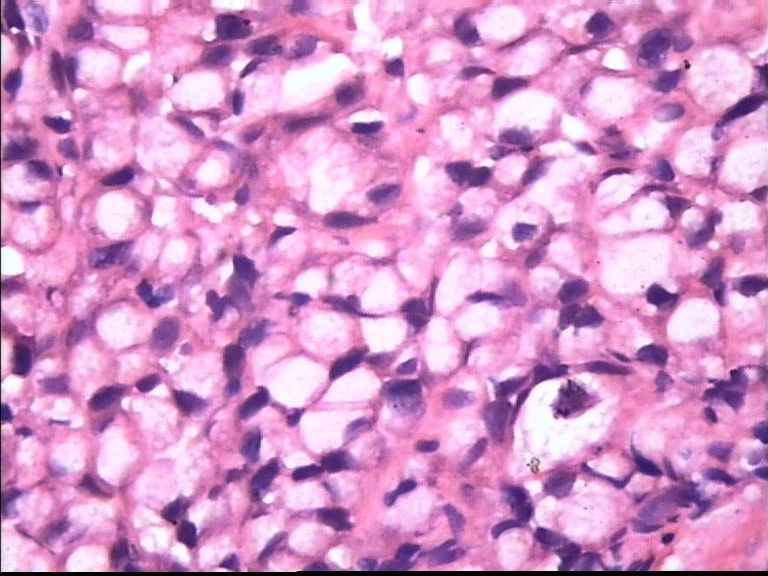

胃部溃疡3cm 53岁 男

仅此局部形态,应该是印戒细胞癌,最好有更多的背景资料

印戒细胞癌

倾向印戒细胞癌

诊断印戒细胞癌

印戒细胞癌高度可疑,建议做:CK、CD68、PAS帮助诊断。